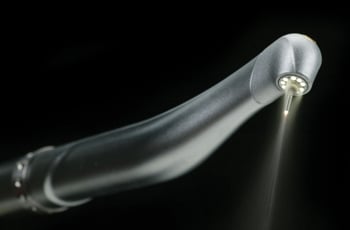

Dr. Hamed H. Javadai of Marin Reconstructive Periodontics utilizes the newest in Waterlase MD, which is a revolutionary dental device that uses a combination of laser energy and water to perform many traditional dental procedures without anesthesia or pain.

The Waterlase MD, uses a less invasive approach that conserves healthy tooth structure, which helps teeth function better and last longer.

Laser Surgery with Waterlase

The Waterlase MD is a revolutionary dental device that uses a combination of laser energy and water to perform many traditional dental procedures without anesthesia or pain. The Waterlase MD, uses a less invasive approach that conserves healthy tooth structure, which helps teeth function better and last longer.

When the traditional dental drill is used, heat and vibration are the major causes of most of the pain. The Waterlase MD works so fast and avoids both heat and vibration, so the tooth nerve can't respond to register pain. This means no shots or the numb feeling after the dental visit.

The Waterlase MD can also perform many soft tissue or gum procedures with little or no discomfort or bleeding.